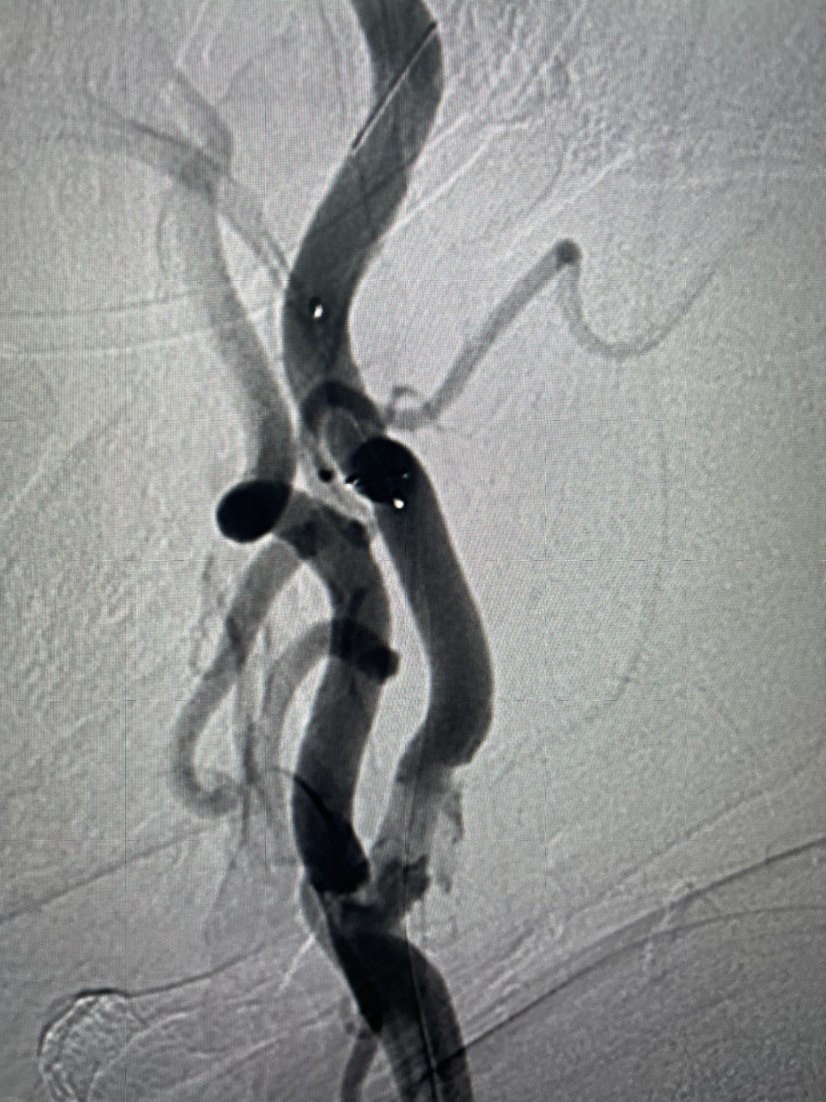

Spider保护伞到位

5mmx30mm球囊扩张

球囊扩张后颈内动脉起始部狭窄明显好转

颈动脉支架植入